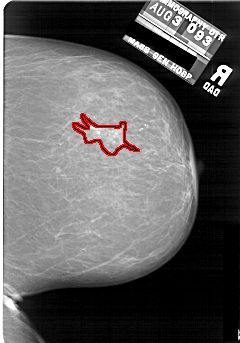

A_1690_1.LEFT_MLO

FILE: A_1690_1.RIGHT_MLO.OVERLAY

TOTAL_ABNORMALITIES 1

ABNORMALITY 1

LESION_TYPE CALCIFICATION TYPE AMORPHOUS DISTRIBUTION CLUSTERED

ASSESSMENT 4

SUBTLETY 4

PATHOLOGY BENIGN

TOTAL_OUTLINES 1

BOUNDARY